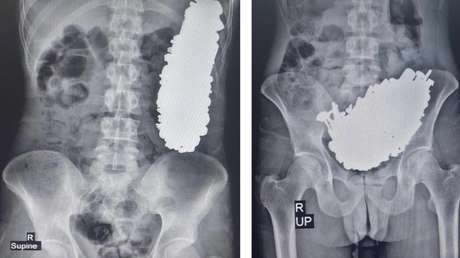

El cuerpo de Kaydell fue repatriado al Reino Unido tres días después, pero más tarde se descubrió que le faltaban partes del corazón e intestinos. Mientras tanto, desde la administración de la clínica aseguraron que el cadáver intacto fue sometido a una autopsia para determinar la causa de la muerte.